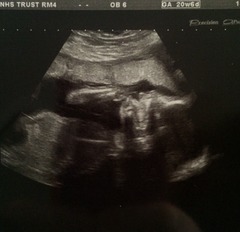

Had my anomaly scan this morning..everything looks perfect and baby was an angel! Although he wouldn't stop munching his hand to get a good face picture, but it's okay, cause I love it anyway! Grin she also confirmed he's definitely a boy.."not shy" were her words haha! Oh and his legs are measuring almost 23w so looks like he'll be tall!

Will attach scan picture and bump picture hopefully!

20+6